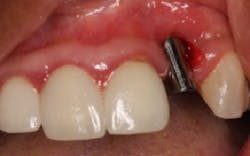

The patient presented to restore the implant six months later with a predicted large vertical and horizontal tissue defect (figure 3). The implant was restored with gingival ceramics to compensate for the ridge defect (figure 4).

The patient was very pleased with the final outcome (figure 5), even though this case certainly would not be considered an esthetic success. Because of the patient’s concerns and low smile line (figure 6), this case was completed six months postextraction and in a cost-efficient manner.